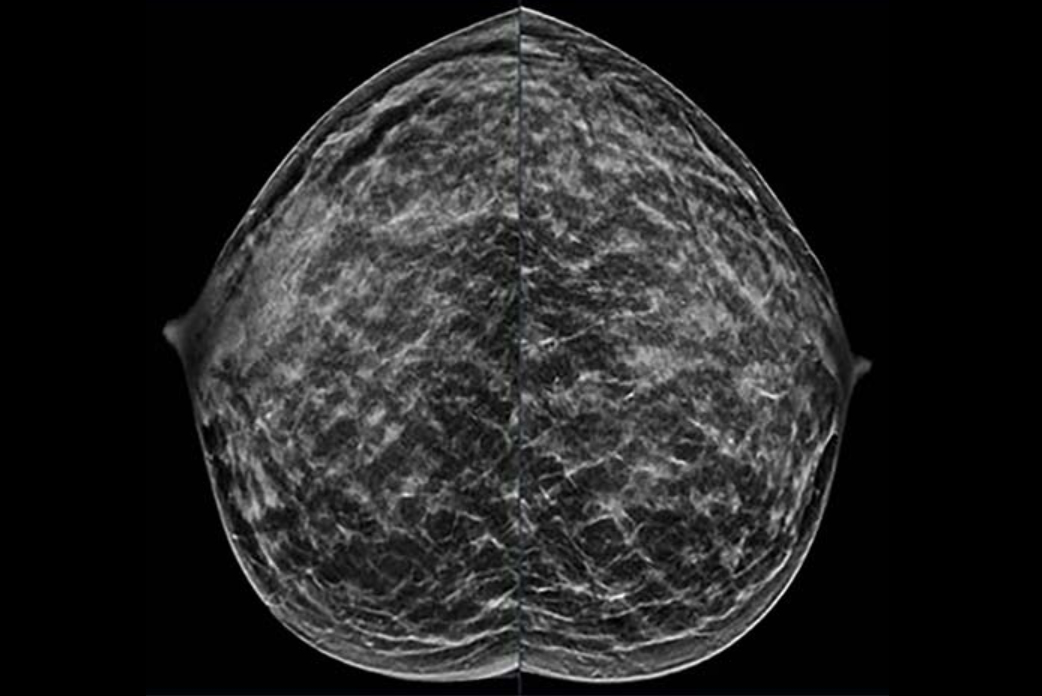

A team led by Meredith Shiels, PhD, from the National Cancer Institute (NCI) also found that early-onset cancer incidence rates increased during the study period, with breast (female), colorectal, kidney, and uterine cancers contributing the largest number of additional early-onset cancers in 2019.

The final analysis included over 2 million cases of early-onset cancer diagnosed between 2010 and 2019. Of these, 63.2% were diagnosed in women. Breast, thyroid, and melanoma were the most common cancer types during this period for women, while for men, colorectal, testicular, and melanoma made up the most common cancer types.

About 80% of additional cancer diagnoses compared to 2010 consisted of female breast cancer, colorectal cancer, kidney cancer, and uterine cancer.